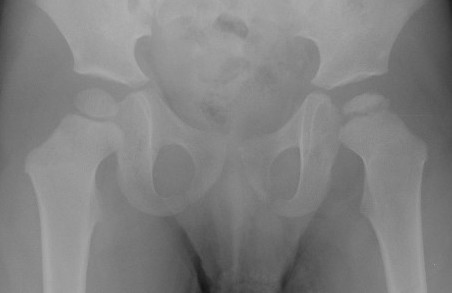

Bilateral - between 8 - 24%

- will not be symmetric

- if symmetric think other causes

MED

- bilateral and symmetrical

- acetabular involvement

- no metaphyseal cysts

- other physeal involvement therefore consider skeletal survey in those with bilateral "perthes"